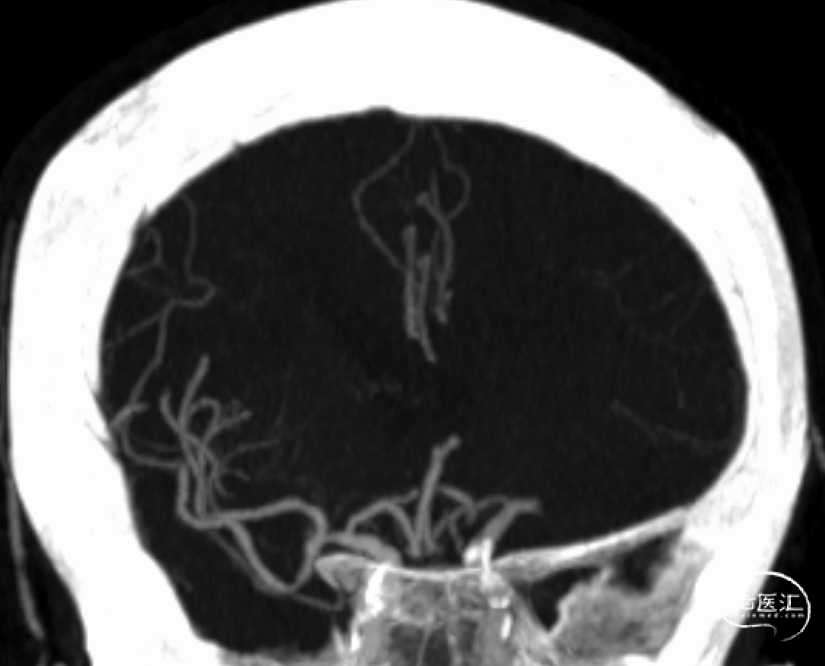

动脉早期冠状位残端

动脉晚期冠状位脑膜支逆流

动脉晚期矢状位脑膜支逆流

多模式影像学评估可协助血管闭塞性质的判断,特别是多时相CTA扫描;